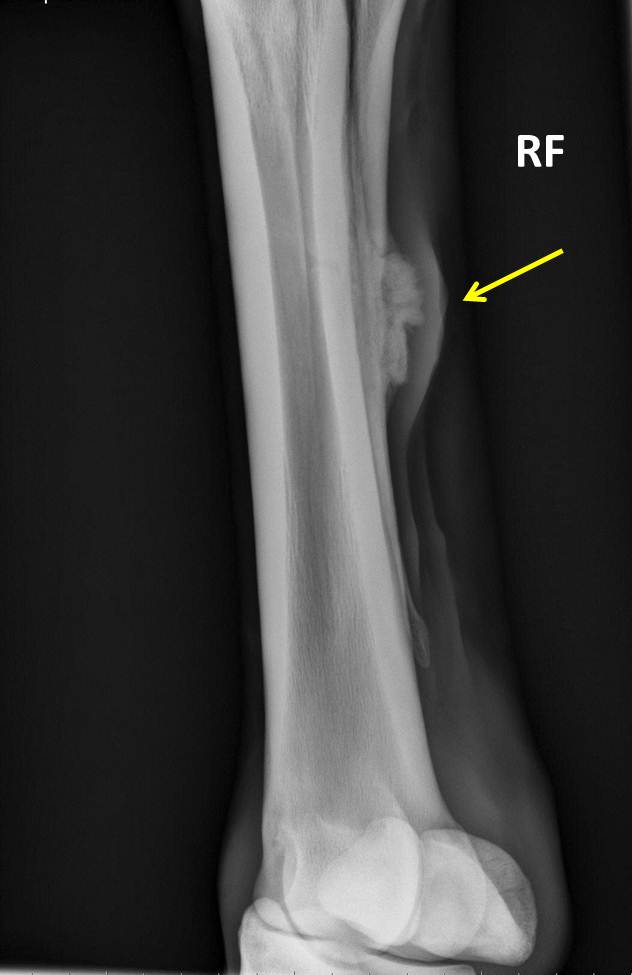

Fracture of Cannon Bone, Complete Horse Side Vet Guide Shin Splints Horses  Saucer fractures can also be referred to as sore shins or bucked shins, that can arise when a horse experiences high levels of exertion whilst being worked or as a result of being exposed to hard and uneven surfaces when they are not fully conditioned. You can manage most splints easily with help from your veterinarian, minimal downtime from exercise,. Shin Splints Horses.